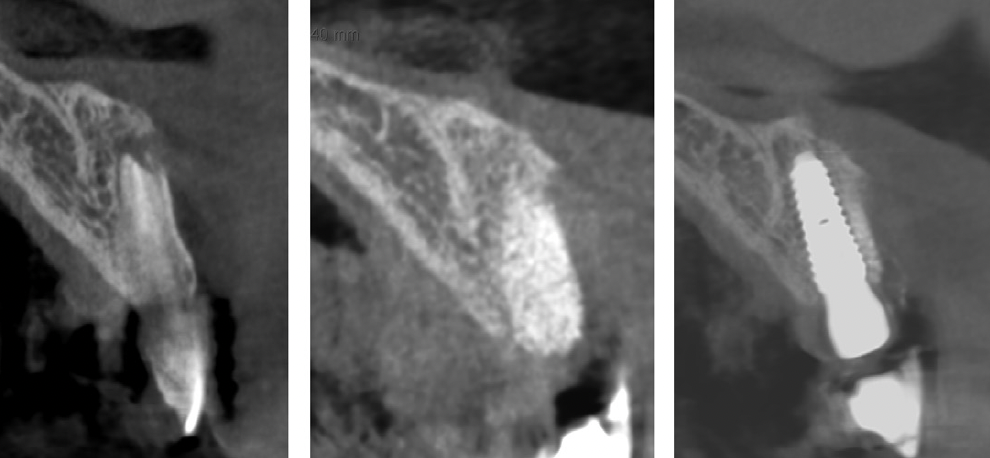

Pentru evitarea pierderii osoase, în anumite cazuri, medicul poate reconstrui imediat postextracțional alveola dentară astfel încât resorbția să fie minimă (Fig. 7.4.1).

Figura 7.4.1 Reconstrucția imediată postextracțională a alveolei incisivului central și aplicarea impl7a.4.n1 tului după 4 luni